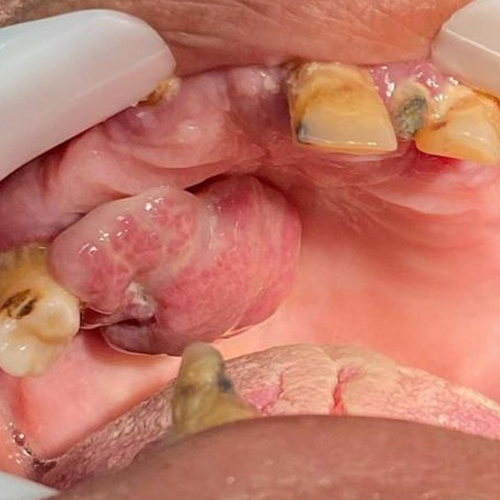

۲) فیبرومای تحریکی: ضایعه تومورال روی لثه و مخاط به ویژه در زنان میانسال و شایعتر در فک پایین. خوش خیم است و بهتر است که به وسیله جراحی حذف شود. فیبروم مرکزی داخل استخوان شکل میگیرد و باعث تخریب استخوان هم میشود.

تصاویری از تومورهای دهانی